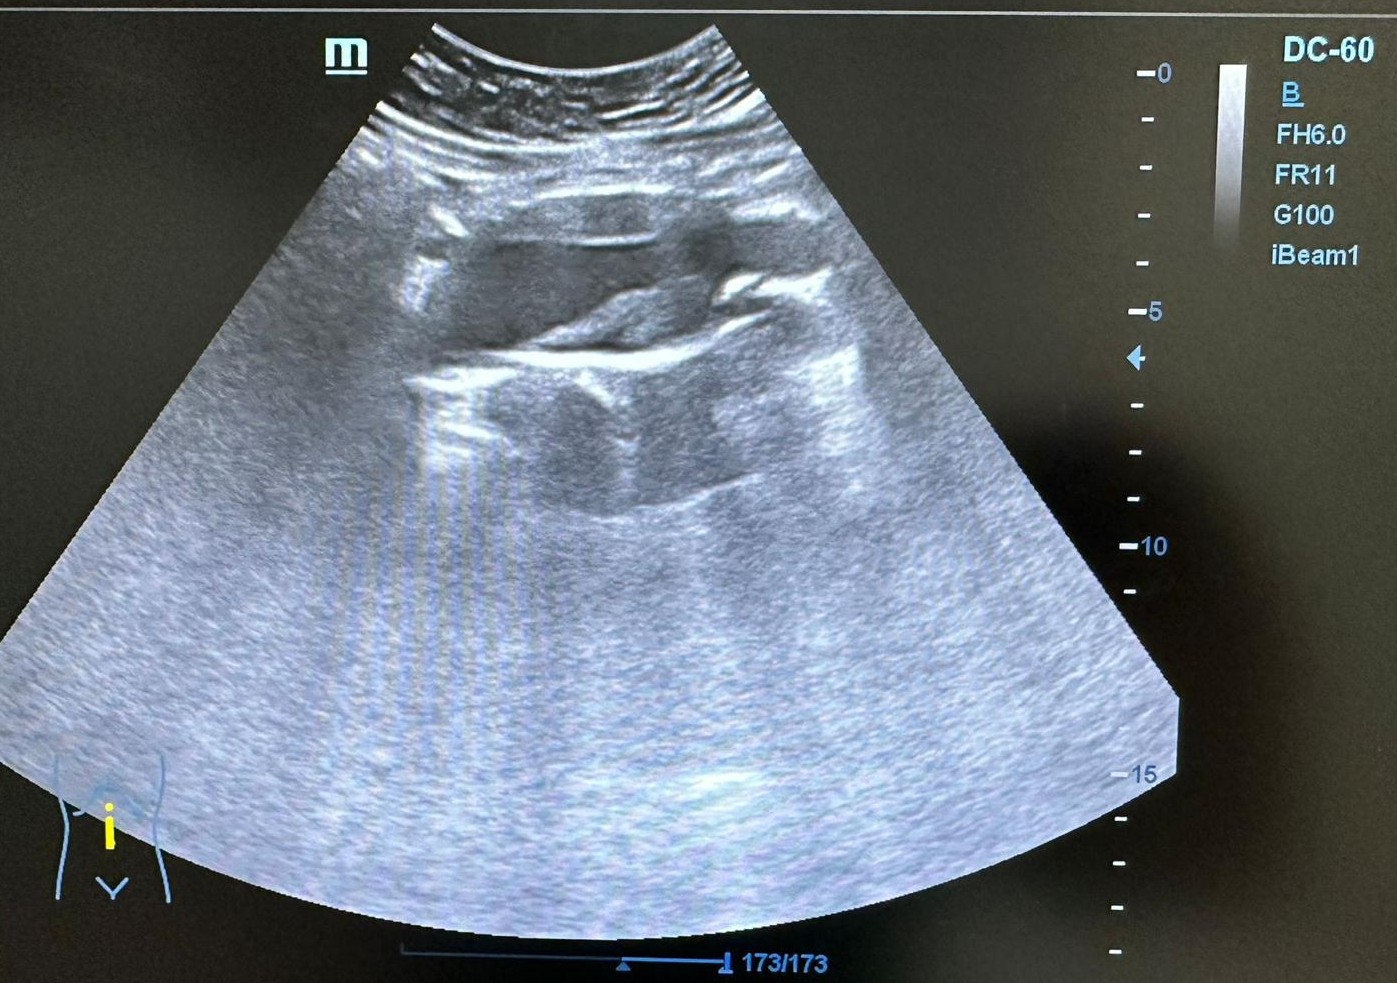

Ecografía clínica AP con los hallazgos siguientes: Presenta dilatación aneurismática de aorta infrarrenal fusiforme con trombo en su interior que disminuye la luz aórtica con diámetro 37,7 x 40,1 mm. Ambos riñones con forma y tamaño normales, buena diferenciación córtico medular sin signos de uropatía obstructiva.